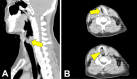

We experienced two cases of post-intubation laryngotracheal stenosis (PILS) occurring in patients after acute coronavirus disease (COVID)-19 in a relatively narrow time period. The patients required mechanical ventilation for 9 days in one and 28 days in the other. In both cases, the patients were discharged but later developed symptoms of cough and dyspnea, which were later diagnosed as PILS. Persistent cough and dyspnea are common symptoms in both PILS and the recovery phase of severe COVID-19. For this reason, PILS should be considered in the differential diagnosis post-COVID-19 patients. In addition, the prevalence of PILS may be greater than that of other critical diseases in severe COVID-19 patients.